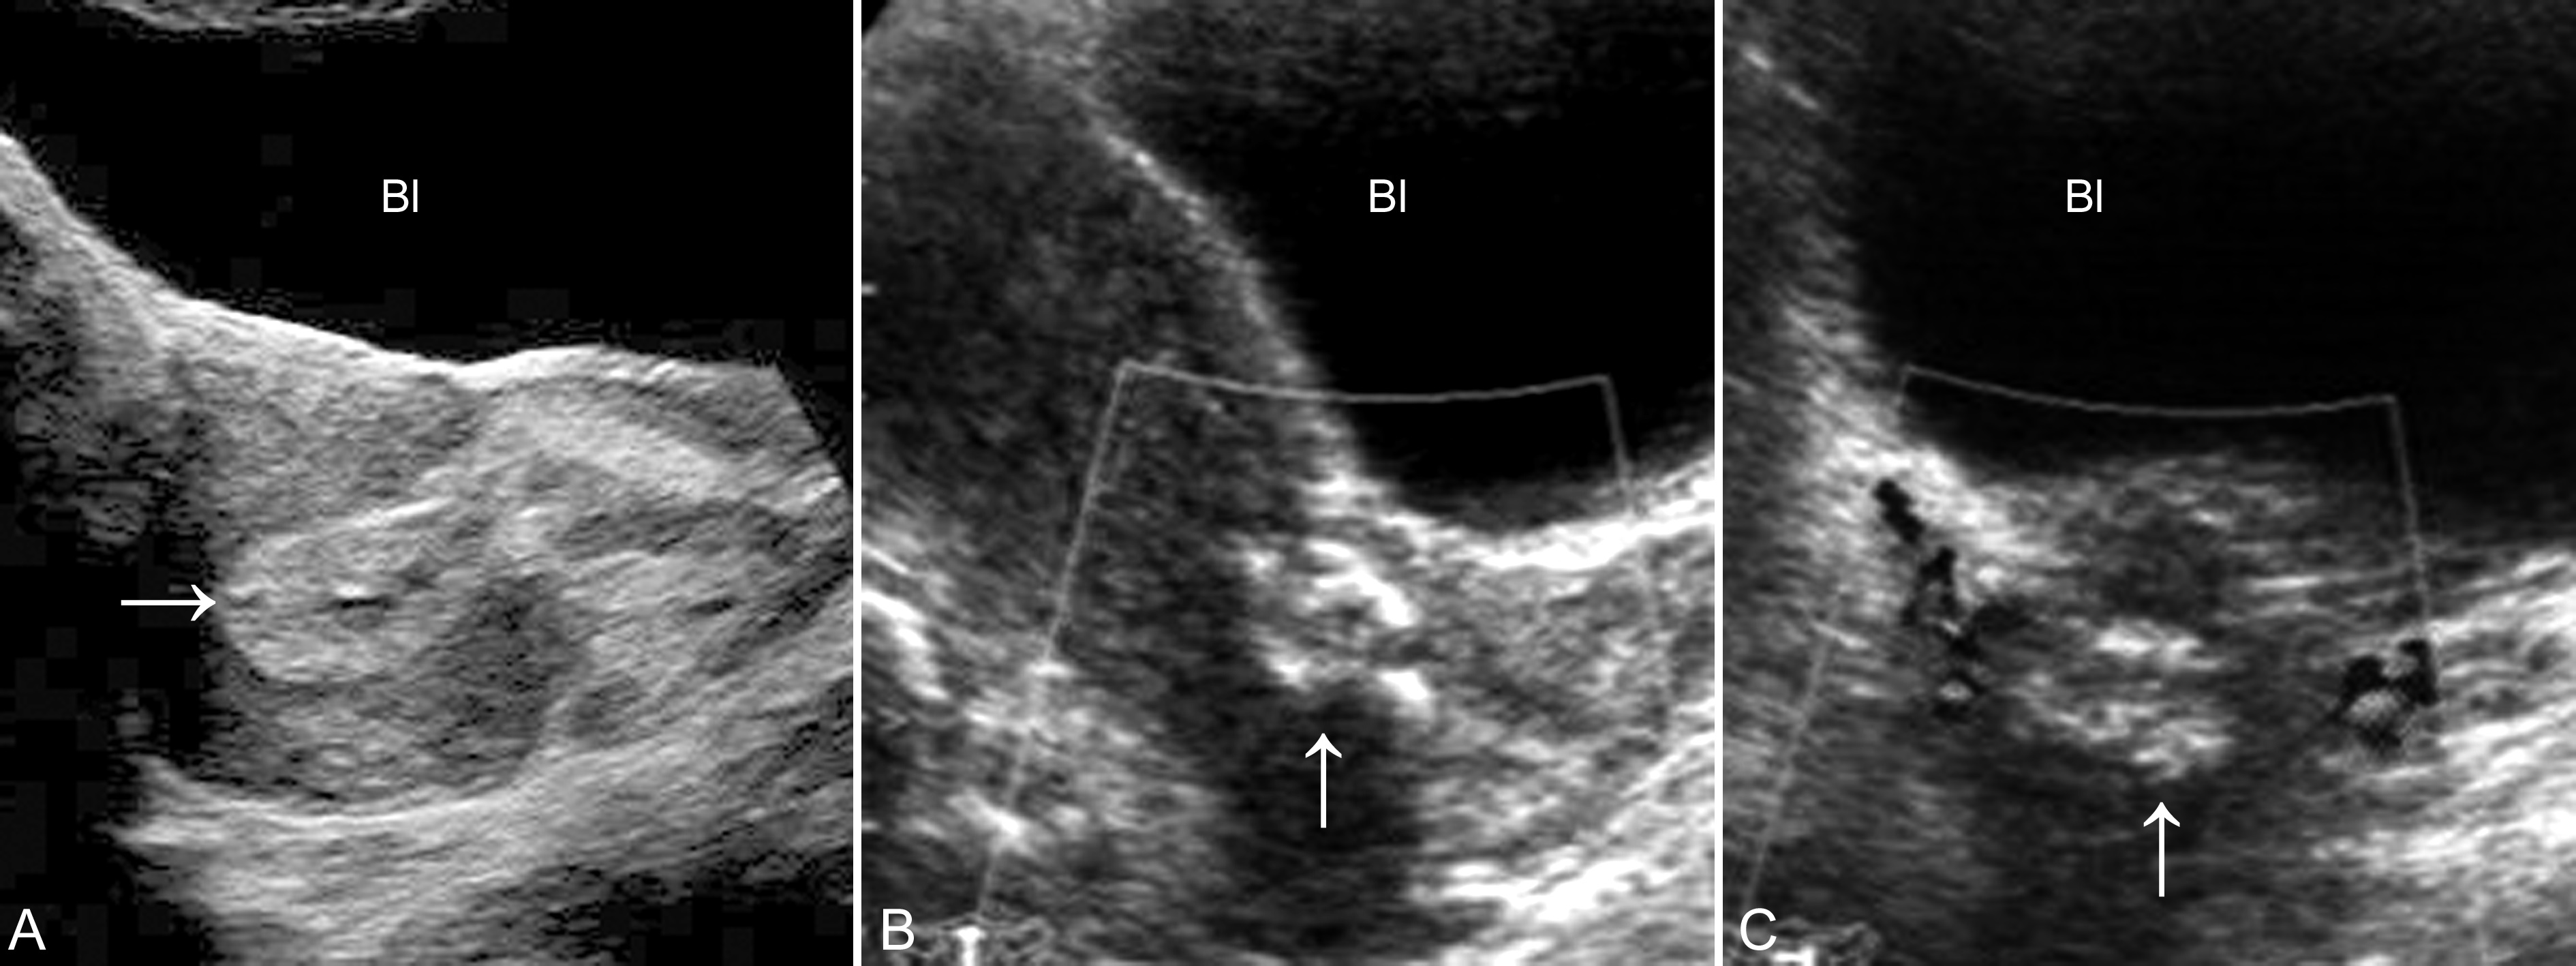

妊娠囊大小正常或较正常缩小,位置下移、变形(图3A)、边缘失去连续性;内部胚胎或胎儿活动消失,心脏搏动明显变弱或不规律、或消失(图3B);如果绒毛膜下血肿超过15ml以上并波及胎盘基底部,即便没有孕囊移位和胚胎死亡,多数也将以流产结束妊娠。

图3 难免流产声象图:变形的孕囊(GS)